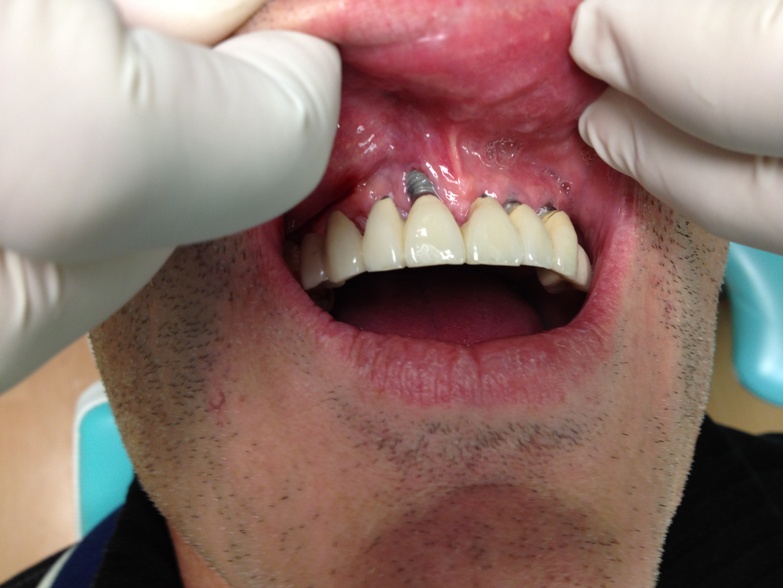

- 5eme cas Madame sylvie Sal qui à reçue une prothèse complète en 2009 chez ………..(oui, c’est bien l’intermédiaire qui m’a indiquer cette clinique, année 2009 en été)En février 2013 elle demande un double de sa radio ………….. Auprès du secrétariat on lui a répondu, qu’un problème informatique est survenu dans leurs système! Plus de radio! de madame Sal pour faire un contrôle ultérieur. Il ne fond pas de radio, ou ils les perdent…les implants du bas on du être enlevez d’urgence en Février 2013 par sont dentiste en France dans le Luberon … Vous pouvez voir état de sa bouche. Publier avec l’autorisation de la patiente.Bonjour,Voilà c’est a cela que ça ressemble, je trouve qu’il y a une différence de couleur.

Celle du gars sont plus grise, les miennes sont plus brillantes….. joli n’est ce pas?? impressionnant!

Et celles du bas ne sachant plus les enlever, tant ça me fait mal…donc rien à vous montrer

Bien à vousSylvie